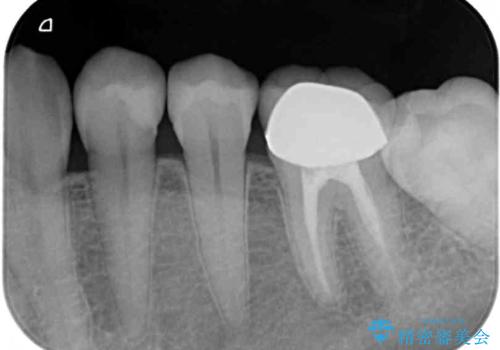

- 冷たいものがしみるとのことで来院された患者様です。

診査を行った結果、第一小臼歯にある樹脂の詰め物(コンポジットレジン)と歯の境目が痛みの原因であることが分かりました。

また、隣接する第二小臼歯も虫歯になっていることも分かったため、2歯を同時に治療するにしました。

下顎の目立つ位置であるため、セラミックインレーによる修復治療を行うこととしました。

精密に型取りを行ったセラミックインレーを装着したことで、治療後にはしみたり痛んだりという症状は治まりました。